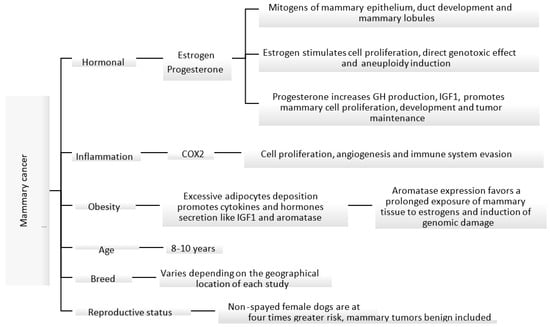

Figure 1.

Known mechanisms and factors involved in the induction of canine mammary cancer [31,35,36,37,38,39].